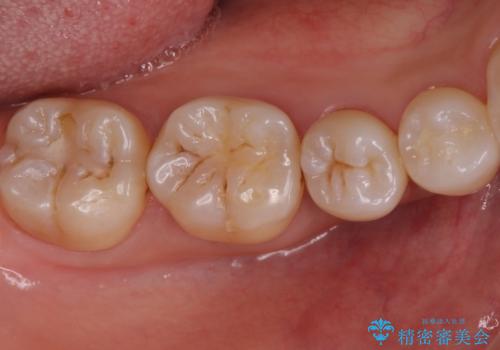

欠けてしまった奥歯 セラミッククラウンとセラミックインレーによるむし歯治療